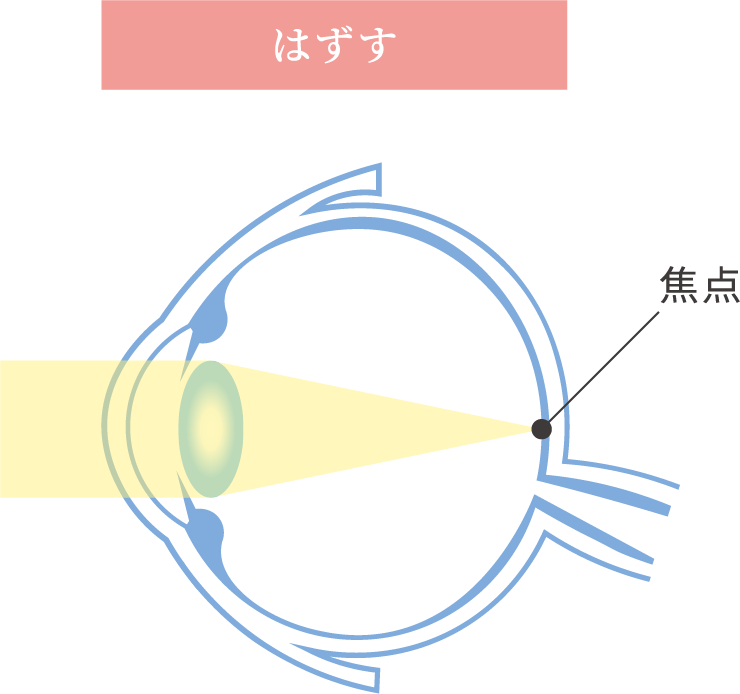

近視は幼児期、学童期、思春期を通し、主に眼の長さが伸びることで、焦点の合う距離が近くなり、焦点距離が近くなればなるほど遠くの像がぼやけてしまいますので、視力が低下します。

近視にはもともと備わっているピント調節機能が関わっています。

眼は近くを見るときには調節力を使ってピントを合わせています。

目にする対象物が近い距離にあればあるほど、この調節力を強く使わなければなりません。

これが問題となり以下の機序が働き、近視は発症し、進行すると考えられています。

- 遠視性デフォーカスと調節ラグ

- 近くを見るときに発生しやすいピントの

合わせすぎのこと

- 軸外収差

- 目の中に入ってきた像を網膜が感じ取りますが、

網膜の中心から少し離れた場所におこるぼやけのこと